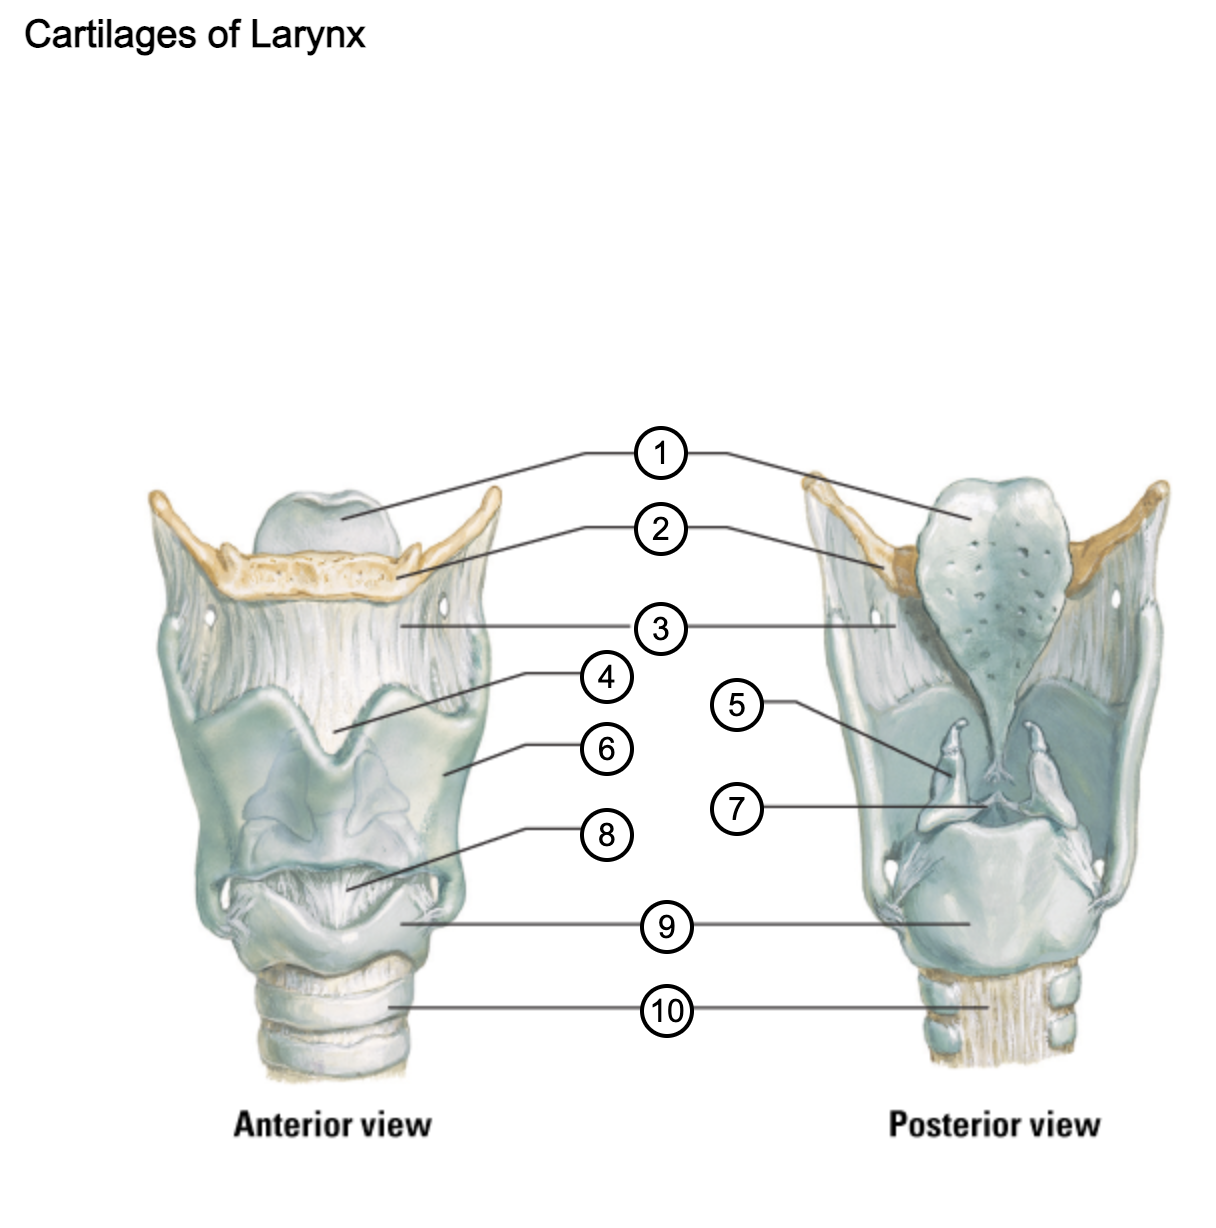

1

epiglottis

2

hyoid bone

3

thyrohyoid membrane

4

superior thyroid notch

5

arytenoid cartilage

6

lamina of thyroid cartilage

7

vocal ligament

8

median cricothyroid ligament

9

cricoid cartilage

10

trachea